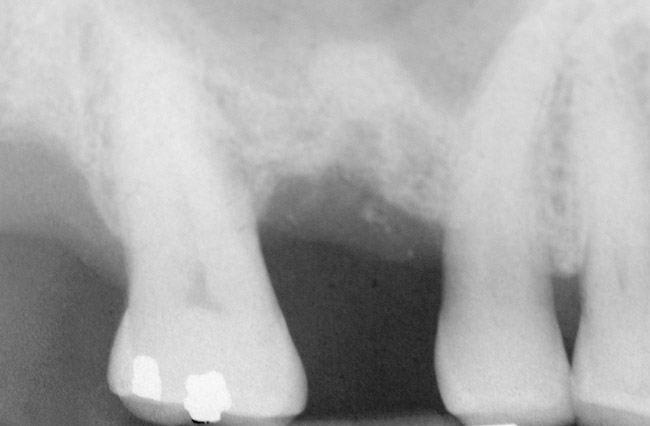

First, a periapical radiograph is taken to determine the amount of bone subantrally. It should be noted that a periapical film has an average error of 14%.23 Therefore, it is advantageous to take the radiograph in a manner that includes a marker (5-mm wide ball bearing) in order to be able to calculate the magnitude of radiographic error (Figure 1).

Figure 1  At tooth site No. 14, a periapical radiograph was taken with the long-cone paralleling technique. The radiographic ball marker measured 5.8 mm while its actual diameter is 5 mm. The enlargement is 0.8 mm, therefore the magnification error is 0.8/5 = 16%. By correcting for this error, a closer approximation of the amount of bone from the osseous crest to the sinus floor can be made.

Figure 1